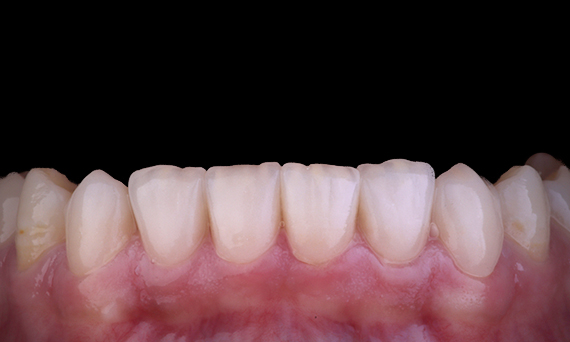

Muchas veces, los pacientes no son conscientes de las grietas o caries que tienen en los dientes. Solo cuando un diente les duele o se rompe, la mayoría de los pacientes se da cuenta de la necesidad de revisarse los dientes. podemos anticiparnos a problemas como el agrietamiento de los dientes, basándonos en la presencia de grietas existentes, una oclusión intensa o antecedentes de pérdida anterior de dientes debido a una grieta. En este caso, el paciente tenía un premolar superior asintomático fisurado que había sido extraído durante un chequeo rutinario. Se había mostrado al paciente la fotografía del diente y se le había informado de la situación, recomendándole restaurar el diente. Sin embargo, el paciente rechazó cualquier tratamiento porque no experimentaba ningún síntoma relacionado con el diente. Seis meses después, el diente se le rompió y el paciente ya no pudo posponer más el tratamiento. El diente se restauró utilizando CEREC con una corona/onlay híbrida de cerámica y resina en una sola visita.

Dr. Sahil Soni, Queensland, Australia